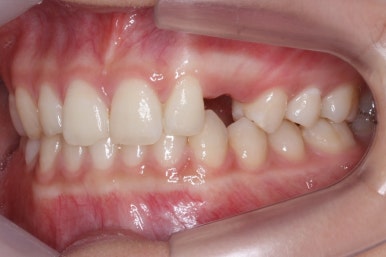

전반적인 비율이나 돌출감 등등 모두 양호합니다. 대신 왼쪽은 송곳니 대신 썩은 유치가 자리잡고 있어서 입을 벌린 상태에서는 해당 부위가 어두워보이고 마치 치아가 없는 것처럼 느껴지기도 합니다.

위 사진들은 부산매복치아교정 키다리아저씨치과에 처음 내원하셨을 때의 모습입니다.

화살표 표시한 부분이 바로 영구치 송곳니가 있어야 할 자리인데, 매복이 되어있고 대신 유치가 여전히 남아있는 모습입니다.